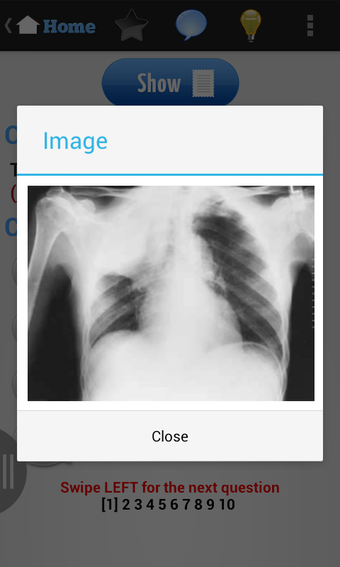

USMLE Exam Prep เป็นแอปพลิเคชัน Android ฟรีที่พัฒนาโดย quizworld ซึ่งเน้นการเตรียมความพร้อมอย่างละเอียดสำหรับการสอบ United States Medical Licensing Examination (USMLE) ให้แก่นักเรียน แอปพลิเคชันนี้ประกอบด้วยภาพพันธุกรรม ไฟล์เสียง และวิดีโอที่ครอบคลุมหลากหลายสาขา เช่น ชีวเคมีและพันธุกรรม รังสีหน้าอก วิธีการคลินิก อายุรศาสตร์ สูติศาสตร์และนรีวิทยา อายุรศาสตร์ประยุกต์ พยาธิวิทยา กุมารเวชศาสตร์ การวินิจฉัยทางกายภาพ ศัลยศาสตร์ จิตเวชศาสตร์ อาการสรีรวิทยา วิธีการคลินิก รังสีหน้าอก และการป้องกันโรค